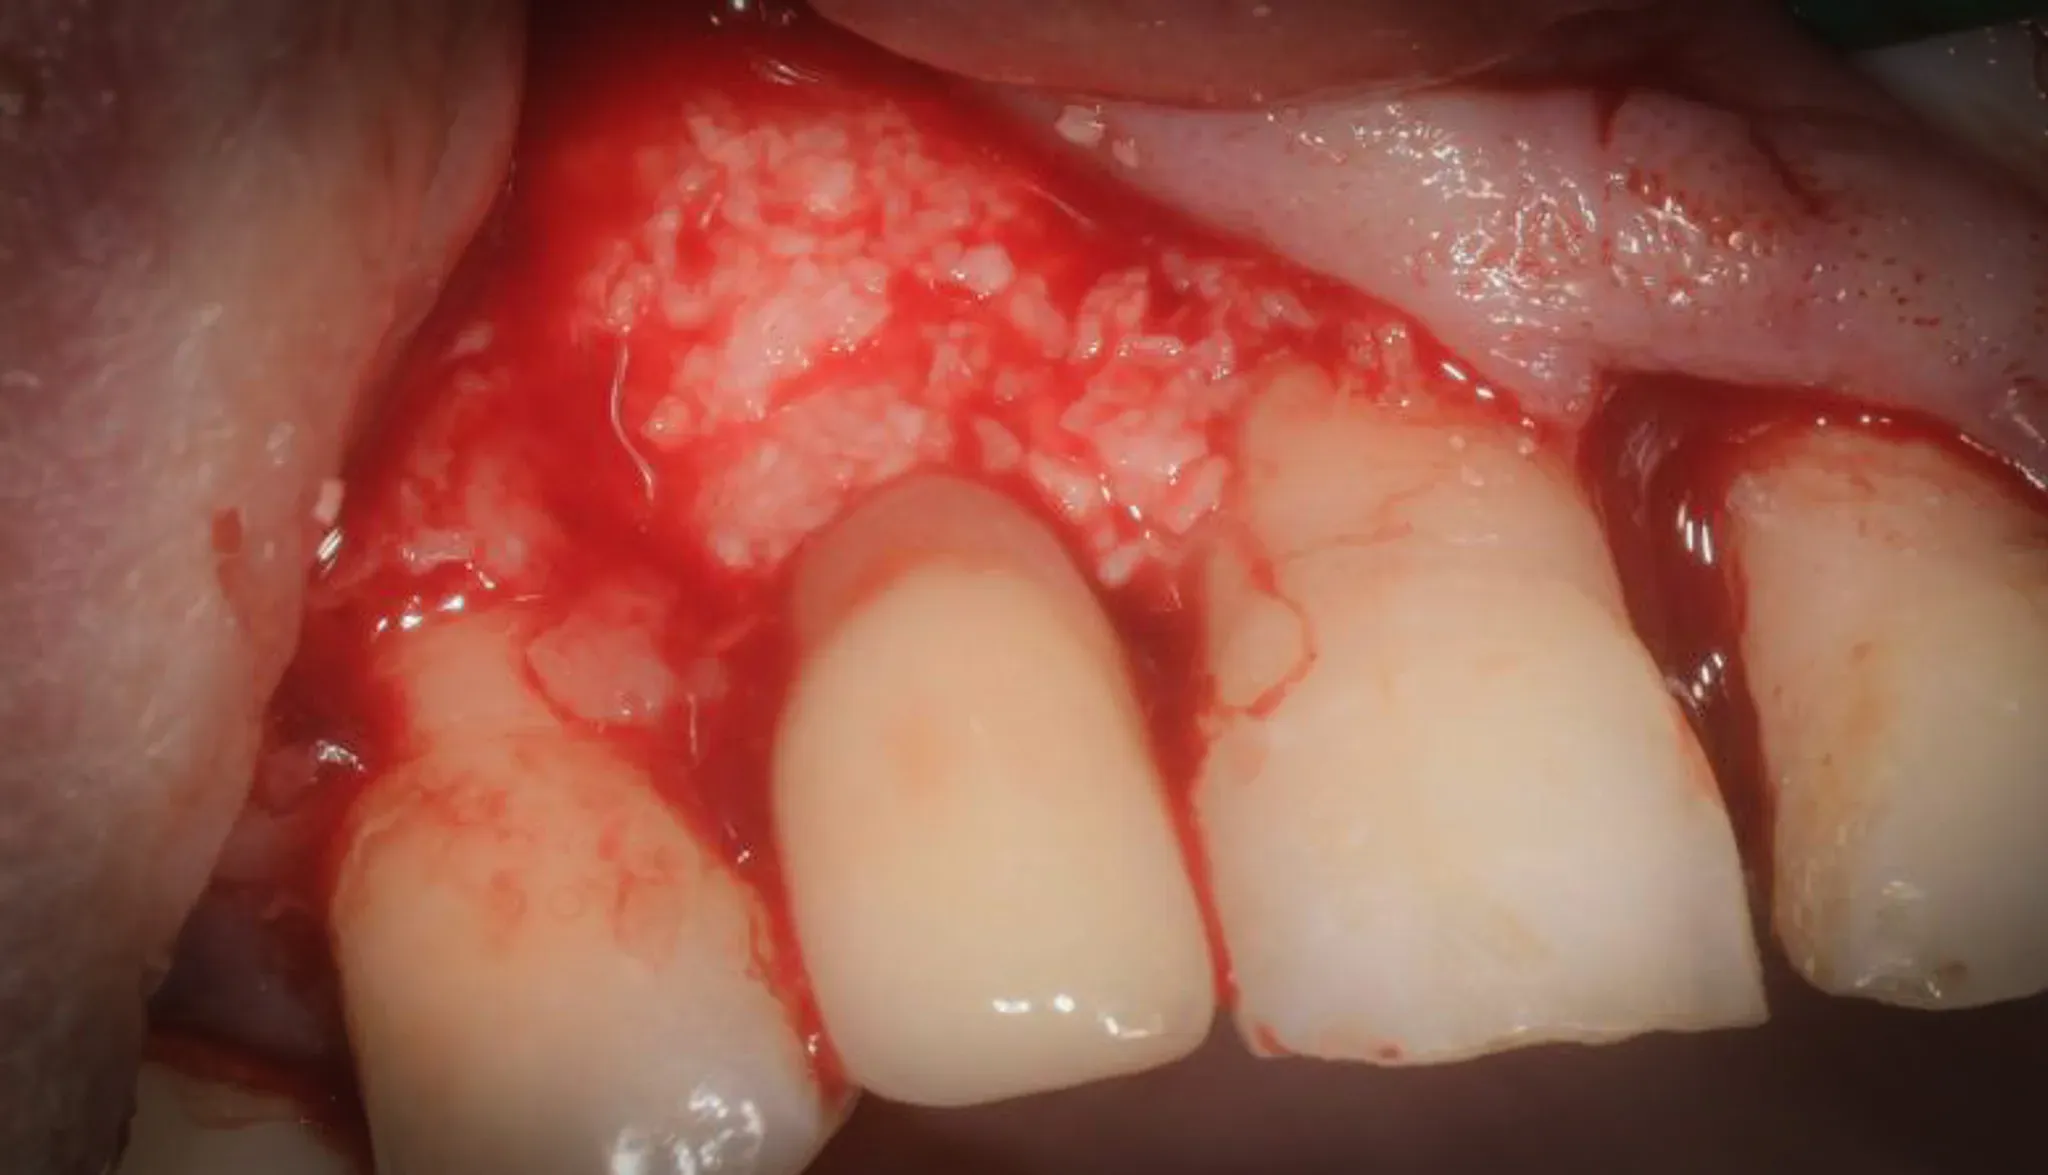

Regeneration

After decontamination, the defect is filled with collagenated porcine xenograft mixed with fibrin glue (Tisseel). Fibrin glue is not a technical luxury: it stabilises the granules, promotes clot adhesion, and keeps the biomaterial in place during the critical early healing phases.